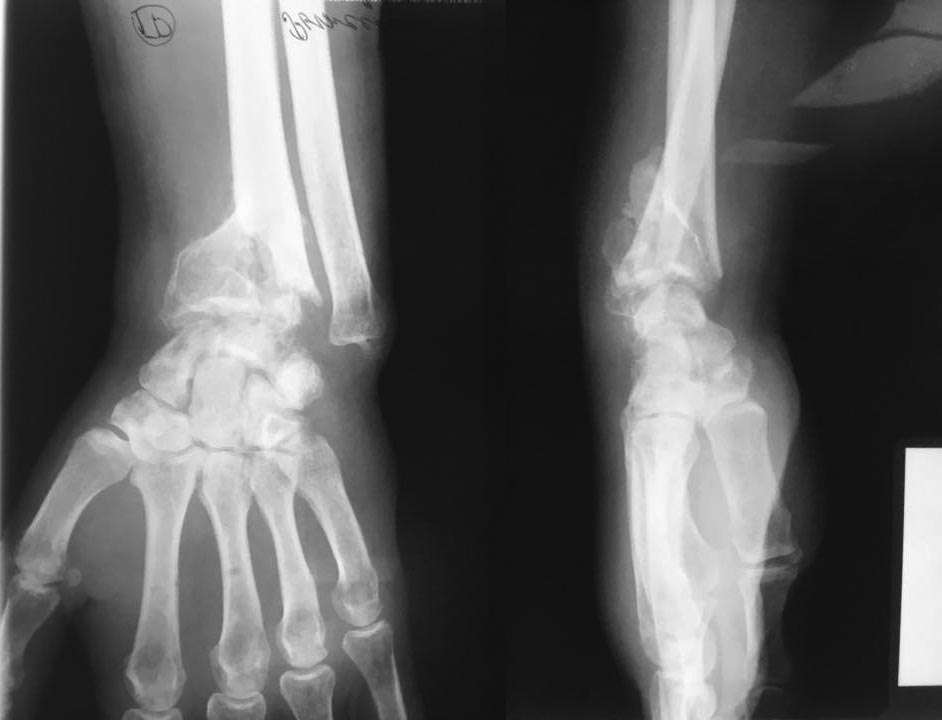

[Ortho] Дистальный луч

Добрый вечер, травма 5 мес назад, лечили гипсом в Ставропольском крае.

Есть предложения?